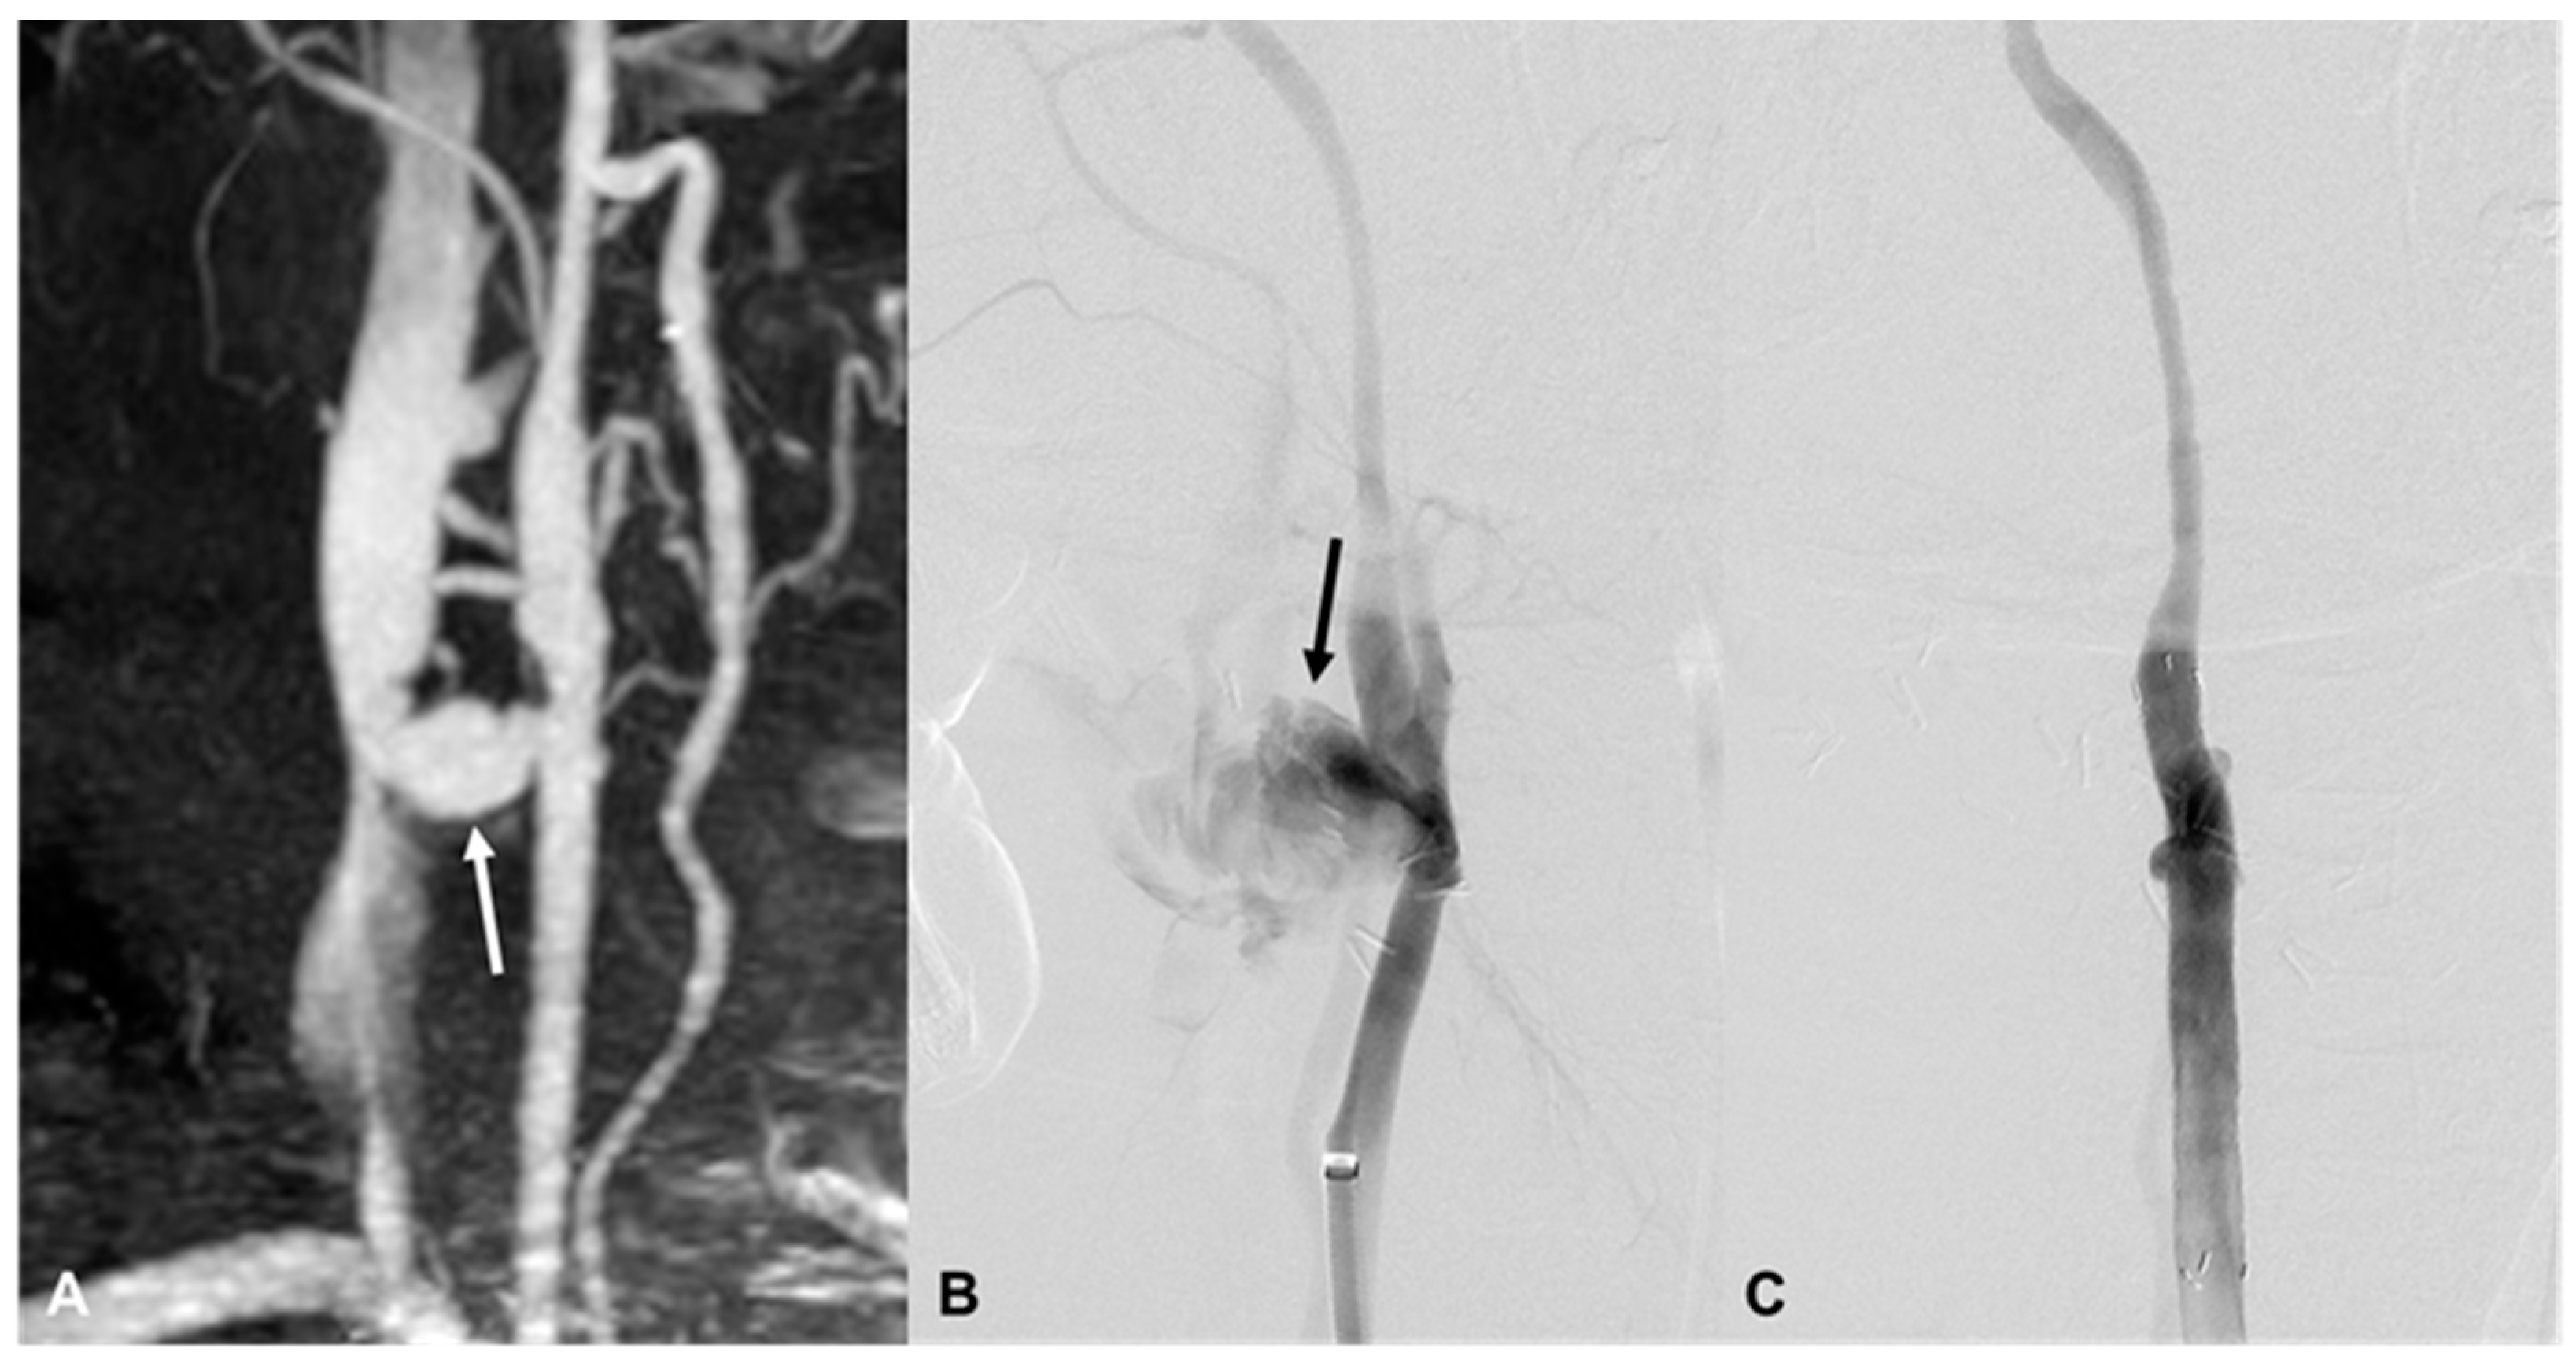

3.5. Vertebral Artery Injury

| 10 | 25/M | Blunt | Ear bleeding | Hematoma, retropharyngeal space | EV, L VA (V2) | bStent, coil | Brain death 12 d |

| 13 | 53/F | Stab | Bleeding | Hematoma, L neck | EV, L VA (V2) | Coil, bStent | Stable 1416 d F/U |